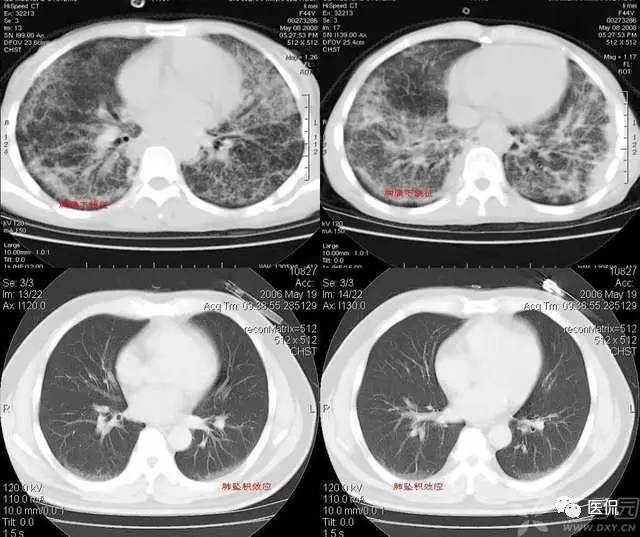

碎石路征

碎石路征或称铺路石征,是胸部CT上的一种影像学征象,主要表现为在弥漫性或散在分布的毛玻璃样浸润影中,有小叶间隔增厚、小叶内线状影重叠存在。碎石路征最初在肺泡蛋白沉积症(PAP)的病例中发现,并认为是PAP特征性的胸部CT表现;但实际上,感染性疾病、肿瘤、特发性肺弥漫性疾病(DPLD)、吸人性病变等都也可以出现。

1、感染:

1)卡氏肺囊虫肺炎(PCP):PCP是由卡氏肺抱子虫引起的肺部机会性感染,多发生于免疫功能严重受损者,是艾滋病(AIDS)患者发生机会性感染和致死的主要原因。PCP的主要症状包括干咳、呼吸困难和低热。典型的胸部X光片改变是双侧、沿肺门周围分布的网状影和境界不清的毛玻璃影;这种改变在CT上则表现为典型的碎石路征。引起碎石路征的病理学基础是:毛玻璃影由肺泡内泡沫样渗出,伴肺泡壁增厚引起;小叶间隔内水肿和慢性炎症细胞浸润致小叶间隔增厚、小叶内线状影。

2)严重急性呼吸综合征(SARS):SARS是一种起病急、病情发展迅速、人群普遍易感、死亡率较高的新的传染性肺部疾病。病理改变主要表现为弥漫性肺泡损伤(DAD),即肺充血、出血、水肿、透明膜形成、肺泡上皮细胞增生,部分肺泡腔内可见到脱屑的肺泡细胞、巨噬细胞和多核巨细胞,伴间质中炎症细胞浸润。主要临床表现是:发热(体温>38℃)、咳嗽、气短、呼吸困难等。胸部X光片可见大片状或斑片状分布实变影。部分SARS患者在起病2周内胸部CT上可发现碎石路征;在疾病的不同时期CT的表现形式有所不同,当早期以分散的、局灶性毛玻璃影为主要表现时,可见碎石路征,继而可以出现实变、间质增厚、胸膜反应和疤痕组织。

2、肿瘤

细支气管肺泡癌起源于细支气管末端的上皮基底细胞,包括无纤毛的Clara细胞、II型肺泡上皮细胞及勃液细胞三种成分。根据癌变的细胞成分不同,可分为赫蛋白性和非赫蛋白性两类。典型的临床表现是患者咯出大量勃液泡沫痰,但不常见,其它表现还有胸闷、气喘、咯血等。根据胸部X光片和CT改变可分为孤立结节型、弥漫性结节型和肺炎型。肺炎型的CT主要表现为毛玻璃影和实变影,文献报道有少数患者的HRCT上可见碎石路征。碎石路征形成的病理学基础是:癌细胞分泌的糖蛋白沉积在肺泡内,呈低密度,在影像学上表现为毛玻璃影,而毛玻璃中间分布的网格状阴影主要是由炎症细胞或肿瘤细胞浸润小叶间隔和肺泡壁产生的。当在毛玻璃影和实变影中发现碎石路征,同时有支气管树僵直,或其它肺野有多发小结节影,或有纵隔淋巴结肿大时,提示肺泡癌。

3、特发性肺弥漫性疾病(DPLD)

文献报道多种原因不明的肺弥漫性疾病的HRCT均可表现为碎石路征,如PAP,结节病,特发性间质性肺炎中的非特异性间质性肺炎、隐源性机化性肺炎等。

1)PAP是一种罕见病。各个年龄均可发病,以20~50岁的成年人多见。干咳、呼吸困难是其最常见的临床症状,而胸膜性胸痛、乏力、低热等则较少见。其胸部X光片表现是双侧对称性的肺泡实变或毛玻璃影,主要分布于肺门及肺门周围而类似肺水肿。CT的典型表现包括:①毛玻璃影及实变影与小叶间隔增厚交织形成碎石路征样改变;②在肺泡实变与正常的肺实质之间出现很明显的分界线,形成“地图样”分布。PAP碎石路征的组织学基础是:毛玻璃影及实变影与肺泡内充满PAS染色阳性、富含脂质的蛋白样物质有关;小叶间隔增厚影与肺泡壁因纤维组织增生或II型肺泡上皮细胞增生及淋巴细胞浸润有关。依据碎石路征和“地图样”分布,结合患者临床与影像学表现不平行的特点,是诊断PAP的诊断的不要依据。

2)结节病是一种原因不明的以非干酪样肉芽肿性炎症为特点的系统性疾病,肺及肺门淋巴结、皮肤、眼等器官均可受累。临床表现因受累部位不同而不同,当肺及肺门淋巴结受累时,可以出现干咳、胸痛及呼吸困难等症状,并常伴有乏力、盗汗、发热、消瘦等症状。常见的胸部X光片和CT的改变是对称性的肺门淋巴结肿大;当肺泡受累时,特别是CT上表现为片状的毛玻璃影时,有时可以出现碎石路征。

3)非特异性间质性肺炎(NSIP)是特发性间质性肺炎中暂定的独立疾病实体,其病理特征是不同区域的间质炎症和纤维化在时相上具有均匀一致性。临床表现与特发性肺纤维化(IPF)相似,表现为咳嗽、呼吸困难,两下肺闻及爆裂音等,但与IPF相比,NSIP预后相对良好。NSIP胸部X光片主要表现为两侧中下肺野毛玻璃影或实变影。最常见的胸部CT异常(80%病例)是毛玻璃影,通常为双侧对称性,主要位于胸膜下及肺基底部。其它改变还有实变影及不规则网状阴影,蜂窝肺较少见。当毛玻璃影与网状阴影重叠存在时,即为碎石路征。当NSIP形成碎石路征时,毛玻璃影提示炎症和纤维组织增生引起的间质增厚,而网状阴影则是肺泡细胞增生、炎症反应和微小纤维化等造成的小叶间隔增厚在CT上的表现。

4)机化性肺炎(OP)过去也被称作闭塞性细支气管炎伴机化性肺炎(BOOP),其病理学特点是远端小气道内肉芽组织增生,填塞气道、甚至累及肺泡腔,伴有肺泡内泡沫样巨噬细胞及间质内炎性细胞浸润。大多数OP为特发性,即隐源性机化性肺炎(COP);少数病例有因可查,如胶原血管病(类风湿性关节炎、混合结缔组织疾病等)、感染、药物毒性反应等常可伴发OP。患者主要临床表现为咳嗽、呼吸困难、发热、白细胞增加、抗生素治疗无效。胸部X光片上可见两肺散在不对称性实变影。大约半数以上患者实变影主要分布在肺周边部。BOOP典型的CT表现实变影在支气管血管束周围或胸膜下分布。BOOP患者的碎石路征并不常见。由托泊替康,博莱霉素等药物诱发的OP,也有个别病例报道其胸部HRCT表现为碎石路征。

4、外源性类脂性肺炎外源性类脂性肺炎(ELP)由急性/慢性吸人动物油、植物油或汽油等物质而引起的肺部疾病。常见的易患因素有咽部结构异常、食管病变(贵门迟缓症、食管裂口庙等)、神经损害、慢性病变等,然而,在许多病例也可以没有易患因素。急性ELP的组织病理学表现是:肺泡外观形态正常,肺泡内充满巨噬细胞,巨噬细胞的胞浆内含有大量脂蛋白样物质。亚急性ELP的病理表现是:肺泡内有大空泡形成,周围有巨噬细胞围绕,肺泡壁及小叶间隔内有炎症性渗出物。反复吸人脂类物质则可导致肺纤维化发生。临床常见的症状有咳嗽、中度发热、气短、胸部不适。胸部X光片的表现通常不特异,包括两肺下叶气腔实变、肺泡实变与间质实变并存;有时还可见到边界不清的局限性大块样病变,与肺肿瘤很相似。胸部CT特点为,实变部位CT值常在-35Hu~-75Hu,提示脂质沉积。同时,ELP也可表现出碎石路征,其中毛玻璃影反映了肺泡和间质内有大量吞噬脂质的巨噬细胞浸润、II型肺泡上皮细胞增生。

5、急性呼吸窘迫综合征急性呼吸窘迫综合征(ARDS)是肺水肿的一种形式,以难治性低氧血症和呼吸困难为特征性表现。休克、挫伤、感染、脓毒血症、吸入毒性物质等是其常见原因。胸部X光片表现为双侧比较均匀一致的毛玻璃影和实变影。早期CT上可见到双肺实变影或毛玻璃影、网状阴影或线状阴影等,肺实变影以背侧最为明显;后期可以有继发性支气管扩张和蜂窝肺形成。当毛玻璃影与网状阴影或线状阴影重叠存在时可形成典型的碎石路征,其组织学基础为毛玻璃影与肺泡内水肿、血管周围腔隙水肿以及富蛋白液体充填肺泡腔、透明膜形成有关。

碎石路征是一种非特异性的影像学表现,多种疾病均可有此改变。熟悉碎石路征的特征,掌握其在各种疾病中出现的部位、特点和其它影像学表现,结合患者的病史、临床表现等,对于缩小肺弥漫性疾病的鉴别诊断范围、降低误诊率及明确诊断有重要的价值。

典型的肺泡蛋白沉积症: